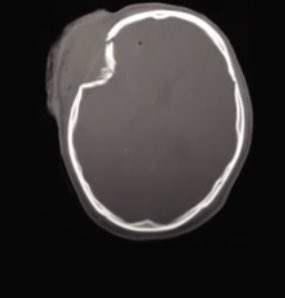

Теменная кость черепа перелом

Теменная кость черепа перелом 111 фотографий